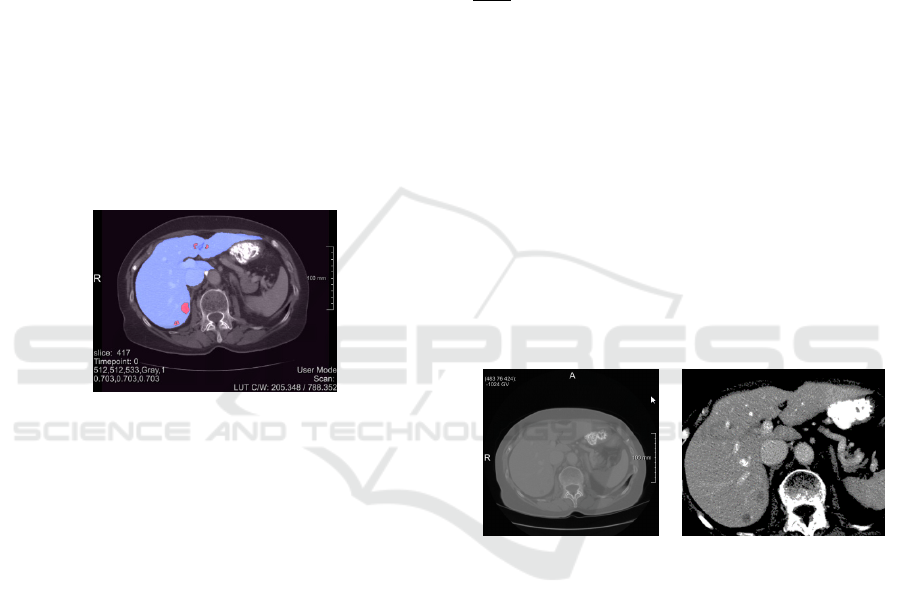

The reference segmentations provided for the liver

liver (1) and liver tumour (2) as shown in Fig.1 for slice

Figure 1: Med Decathlon slice 417 of liver dataset #0 with

parenchyma (blue) and the tumour (red) respectively.